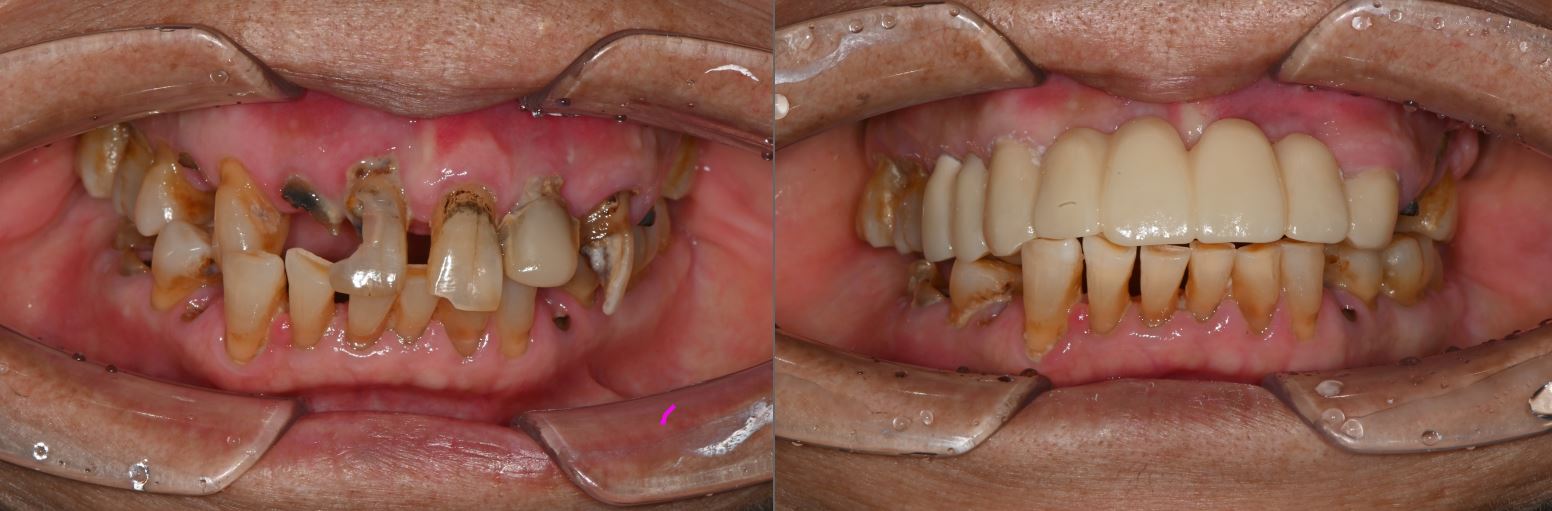

치료전후사진